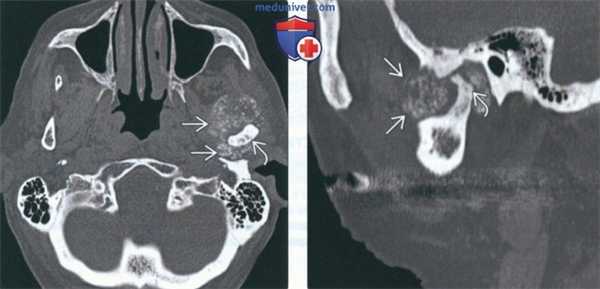

(Слева) КТ в костном окне, аксиальная проекция. Типичная хондросаркома левого височно-нижнечелюстного суаава. Мыщелок нижней челюсти склерозирован и имеет неправильную форму, внутри и вокруг сустава рассеянны множественные кальцификаты. И хотя в данном случае достаточно сложно дифференцировать заболевание от синовиального хондроматоза, в обоих случаях лечение должно быть хирургическим, а точный диагноз будет установлен после гистологического исследования.

(Справа) Реконструкция в сагиттальной плоскости, этот же пациент. Мыщелок деформирован, а часть кальцификатов находится в мягких тканях вне сустава.

(Слева) На аксиальной КТ в костном окне визуализируется типичная хондросаркома ВНЧС с множественными кальцинатами. Мыщелок нижней челюсти слева неравномерно склерозирован, в ВНЧС и вокруг него визуализируются множественные мелкие очаговые кальцинаты.

(Справа) На сагиттальной реформатированной КТ у этого же пациента определяется деформация мыщелка. Некоторые кальцинаты, вероятно, находятся в мягкотканном компоненте за пределами сустава.